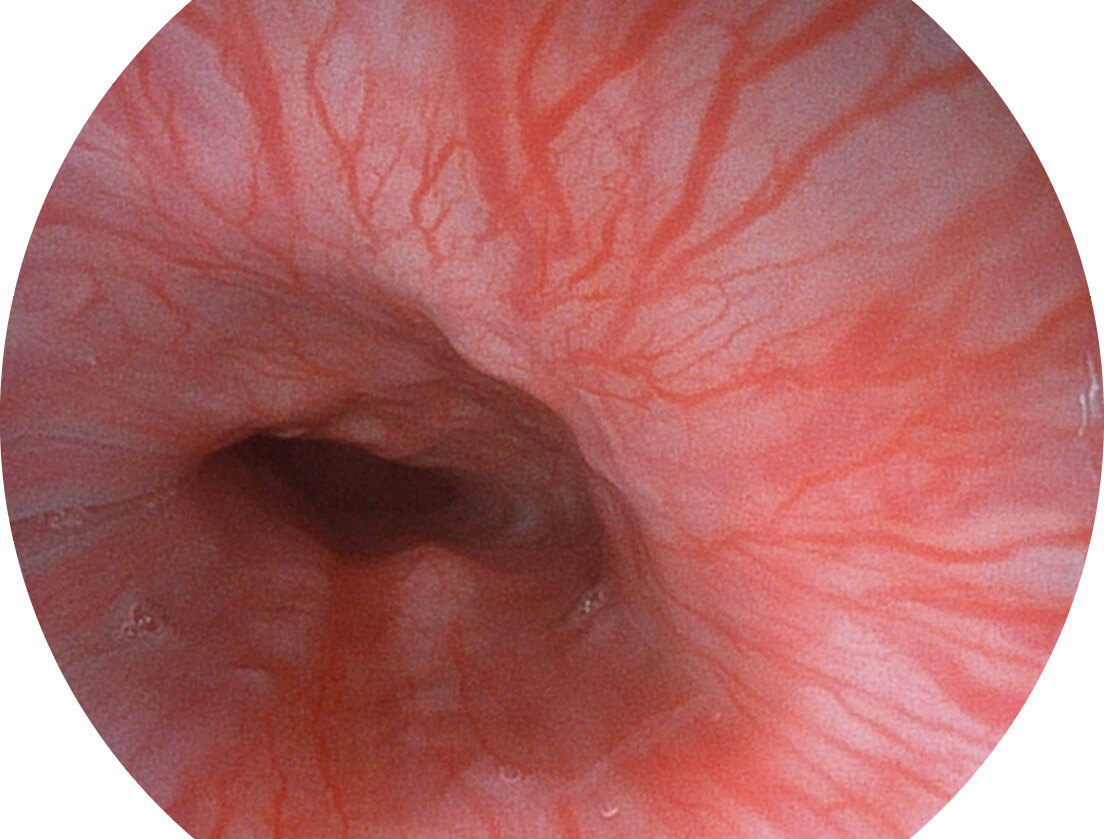

• 白光图像 VIST图像